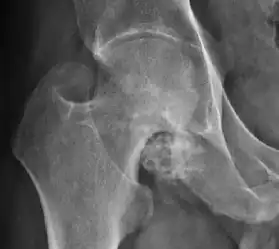

Synovial chondromatosis can be confidently diagnosed by X-ray when calcified cartilaginous chondromas are seen. However, other synovial proliferative processes, such as pigmented villonodular synovitis, require MRI for accurate diagnosis, although noncalcified synovitis can be suspected in radiographs by indirect signs, such as soft tissue swelling and/or erosions in the femoral head, femoral neck, or acetabulum (Figure 7).[1]

Figure 7:

In synovial proliferative disorders, MRI demonstrates synovial hypertrophy. In the case of PVNS, characteristic foci of low signal intensity related to hemosiderin deposition are better seen on gradient echo T2* images (Figure 7). In the case of synovial osteochondromatosis, the synovial hypertrophy is accompanied by intermediate signal cartilaginous loose bodies and/or low signal calcified loose bodies.[1]